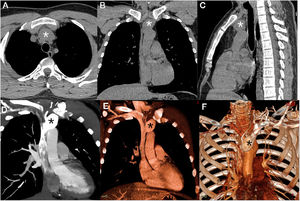

A 33-year-old man with no significant past medical history presented with a mediastinal mass that had been found incidentally on a chest CT examination performed as part of the investigation of a respiratory infection. Non-enhanced chest CT showed a prevascular mediastinal mass (Fig. 1A–C). Enhanced CT with coronal reconstruction (Fig. 1D–E) and 3D volumetric reconstruction (Fig. 1F) demonstrated a fusiform aneurysm of the brachiocephalic vein, extending to the superior vena cava, measuring 2.5cm×2.7cm×3.8cm; its neck was 1.1cm in diameter. A final diagnosis of left brachiocephalic vein aneurysm (BCVA) was made. Some treatment options were offered to the patient, especially antithrombotic treatments. The patient refused any kind of treatment, and is being followed on an outpatient basis. After 3 years, he remains asymptomatic.

Non-enhanced chest CT (A–C) showed a prevascular mediastinal mass (asterisks). Enhanced CT with coronal reconstruction (D, E) and 3D volumetric reconstruction (F) demonstrated a fusiform aneurysm of the brachiocephalic vein, beginning 1.5cm distal to the internal jugular vein and extending to the superior vena cava (asterisks).